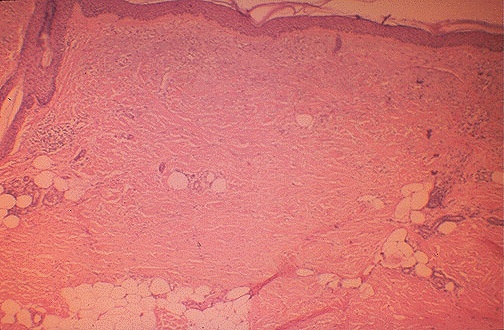

| At low magnification, there is a greater amount and depth of dermal collagen, leading to the decrease in elasticity. Though scleroderma (systemic sclerosis) is an autoimmune disease, the main microscopic feature is fibrosis, and chronic inflammatory cell infiltrates are sparse, unlike SLE. |